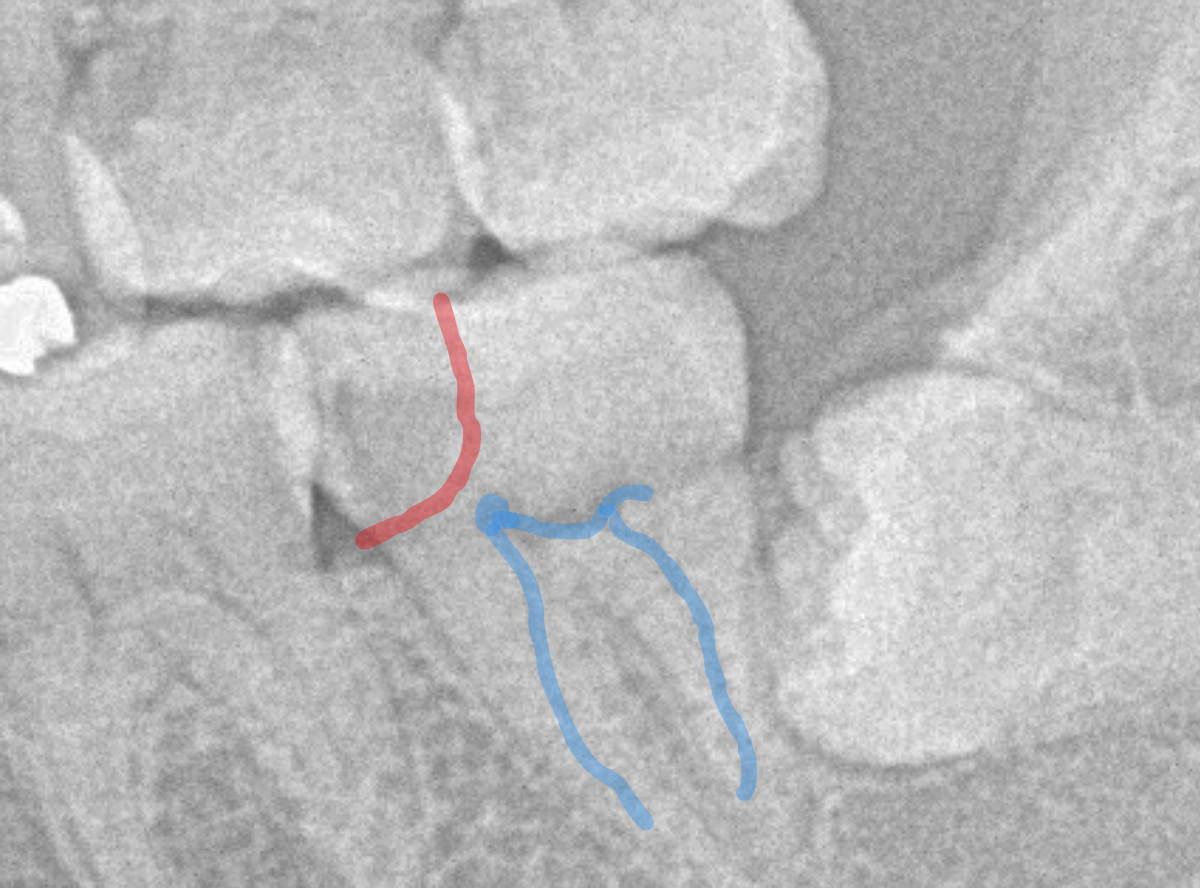

やはり、奥歯の端が大きな虫歯になっています。

青いラインが歯の神経、赤いラインが虫歯です。

レントゲン写真上では虫歯が神経まで達しているように見えます。

これは、神経を取らないとダメかもしれません。